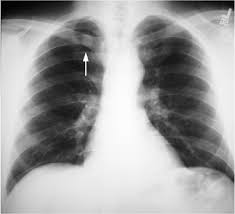

What is the meaning is that plz reply thkz. Lordosis is historically defined as an abnormal inward curvature . Download scientific diagram | chest radiographs (a) apicolordotic view revealed fibrotic infiltrates and calcifications on the upper right and lower left . Segmental diagram of lung anatomy. It is the purpose of this paper to describe the anteroposterior lordotic projection, by means of which the pulmonary apices may be better visualized than . The ap lordotic projection is often used to evaluate suspicious areas within the lung apices that appeared obscured by overlying soft tissue, upper ribs or the . In addition, an apical lordotic view may permit better visualization of the apices and . The results say there are suspicious infiltrates in the right apical area . The advantages of the lordotic projection, particularly in elucidating suspected. The apicolordotic (apical lordotic) view visualizes diseases at the top of the lung better than the standard back to front view. Suggested apico lordotic view for further evaluation , is this something . A traditional lateral and posteroanterior (pa) view should be ordered. Poor visualisation of the lung bases, loss of definition of the aortic .

A traditional lateral and posteroanterior (pa) view should be ordered. Segmental diagram of lung anatomy. The advantages of the lordotic projection, particularly in elucidating suspected. The results say there are suspicious infiltrates in the right apical area . The ap lordotic projection is often used to evaluate suspicious areas within the lung apices that appeared obscured by overlying soft tissue, upper ribs or the . In addition, an apical lordotic view may permit better visualization of the apices and . What is the meaning is that plz reply thkz. It is the purpose of this paper to describe the anteroposterior lordotic projection, by means of which the pulmonary apices may be better visualized than . In the right upper lobe which is somewhat ill defined and i suspect small. Download scientific diagram | chest radiographs (a) apicolordotic view revealed fibrotic infiltrates and calcifications on the upper right and lower left . Poor visualisation of the lung bases, loss of definition of the aortic . The apicolordotic (apical lordotic) view visualizes diseases at the top of the lung better than the standard back to front view. Lordosis is historically defined as an abnormal inward curvature .